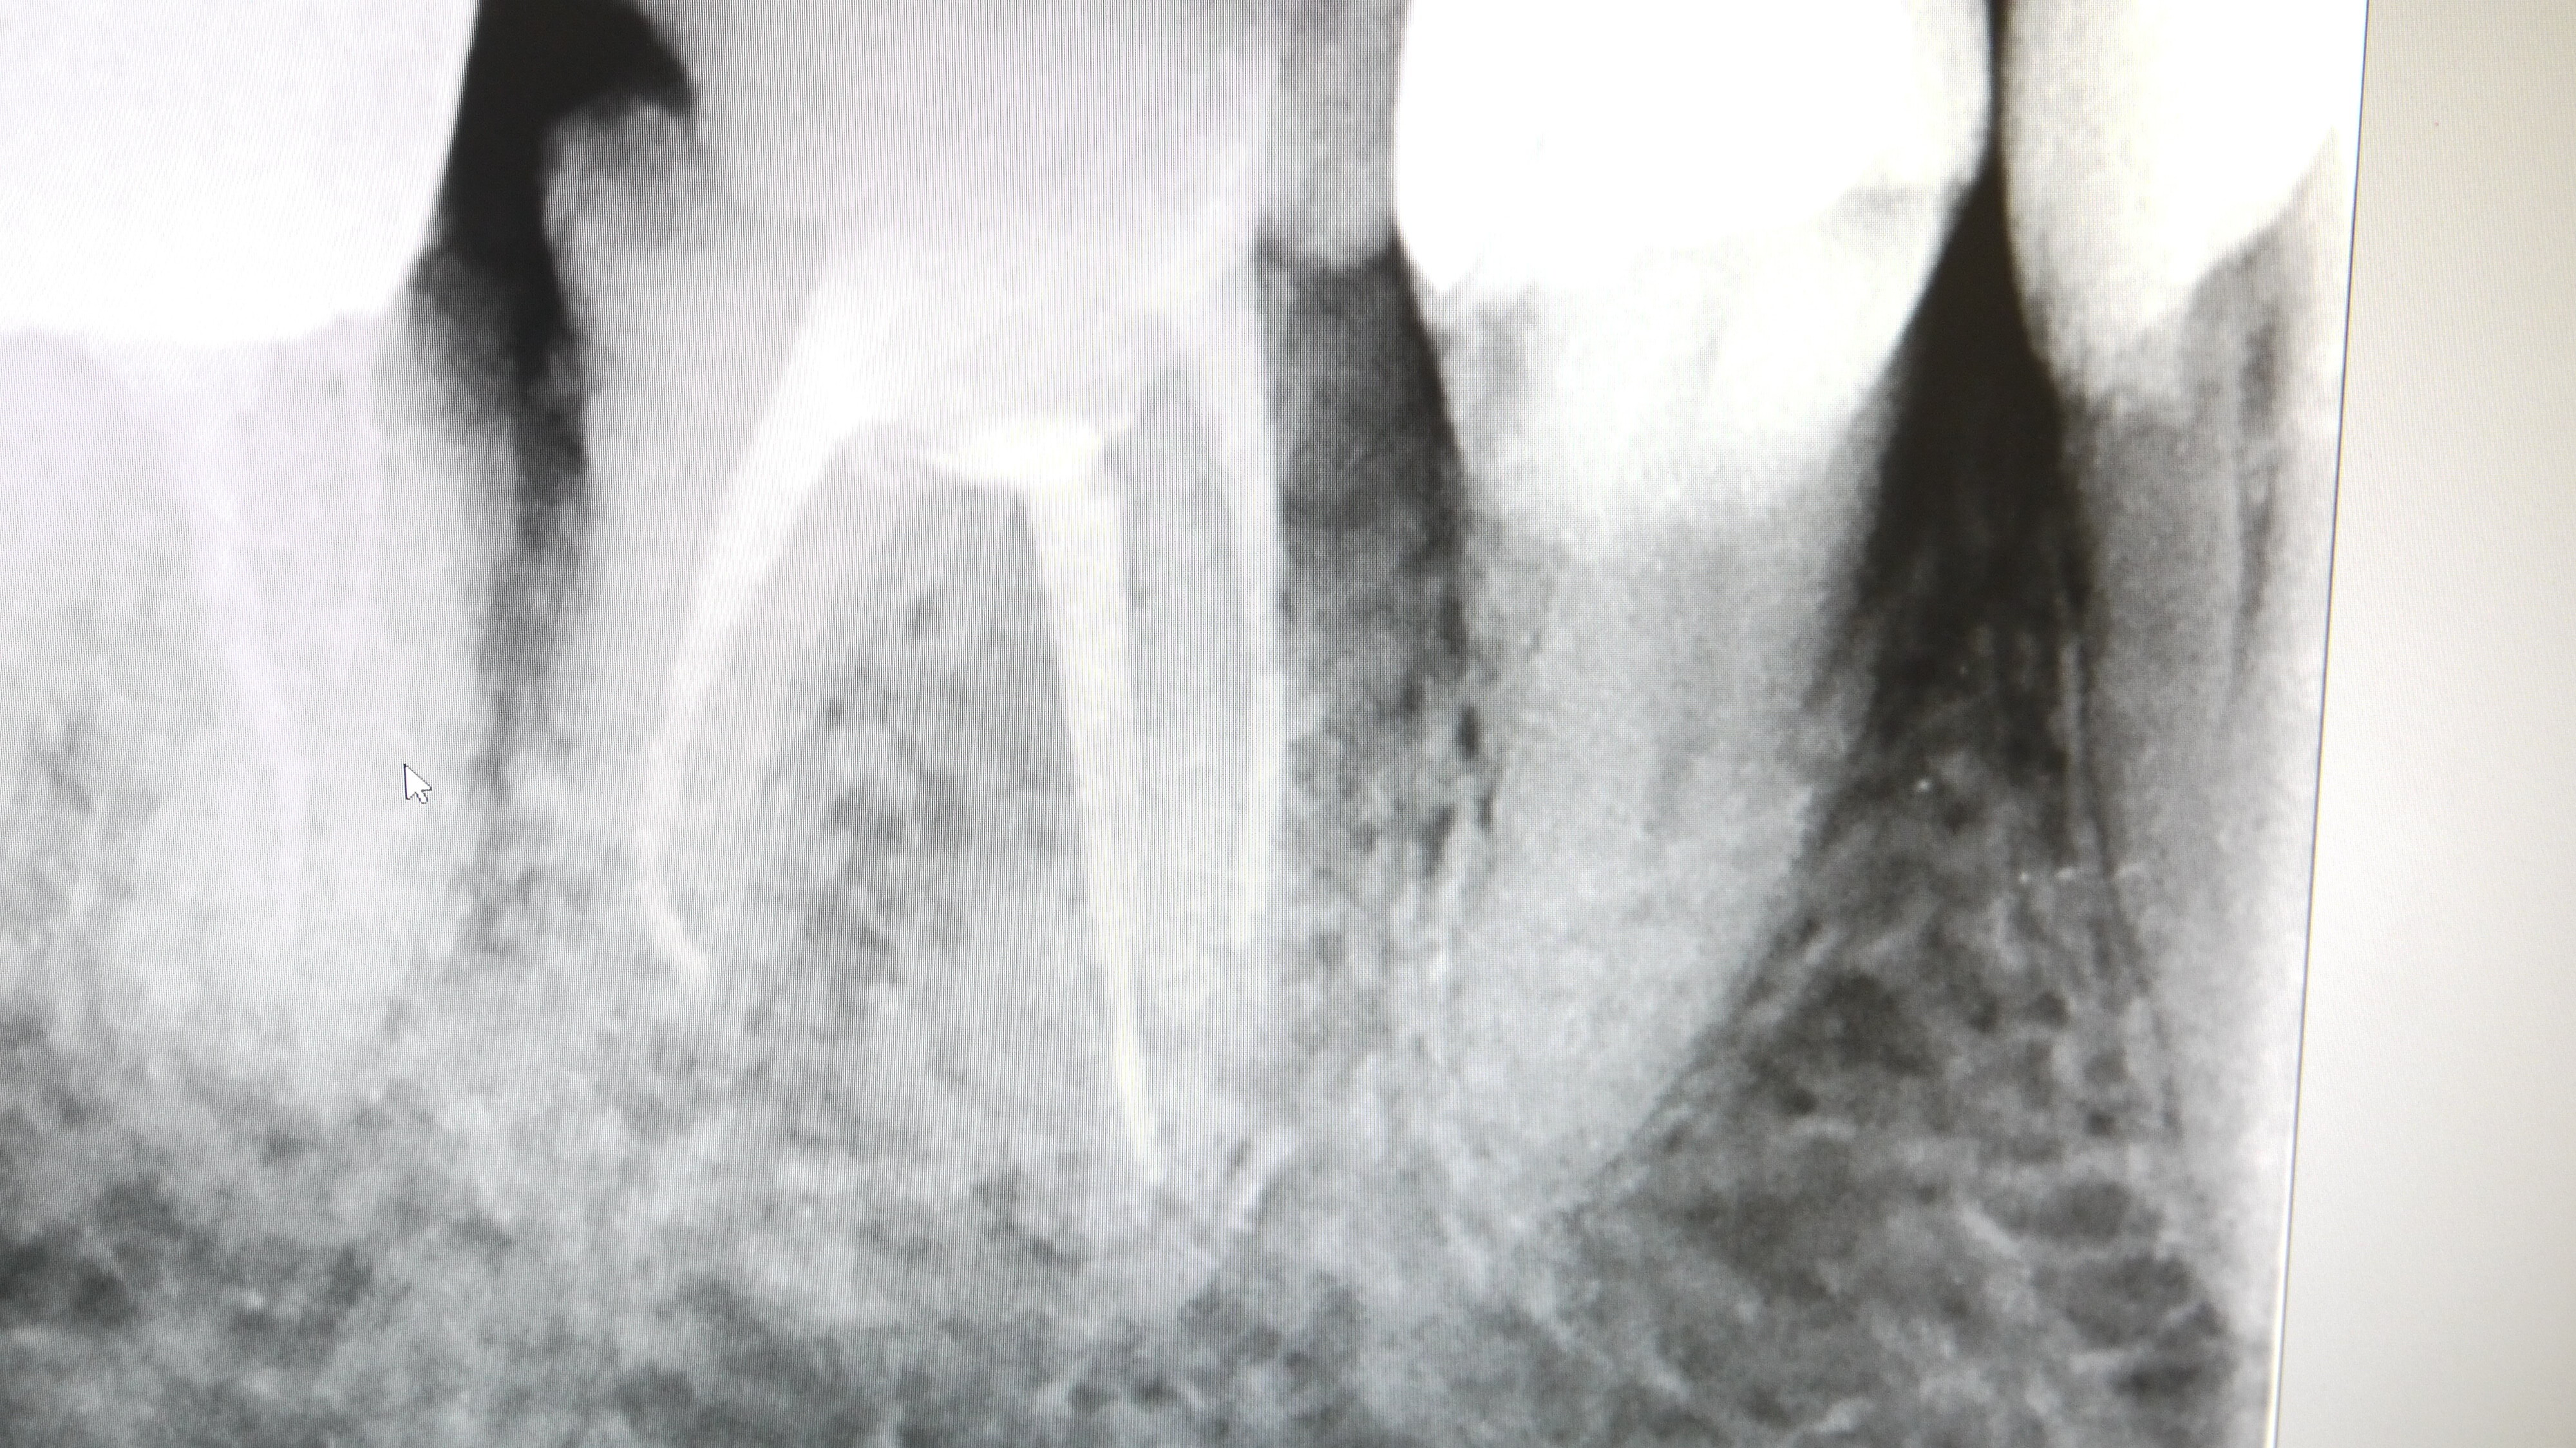

根管の中を無菌状態になるまで消毒し、腫れがなくなったら

根管の中に薬(ガッタパーチャとシーラー)をつめていきます。(根管処置)

この際、根の長さぴったりまで加圧しながら薬を詰めていくことが

腫れの再発を防ぐために最も重要です。